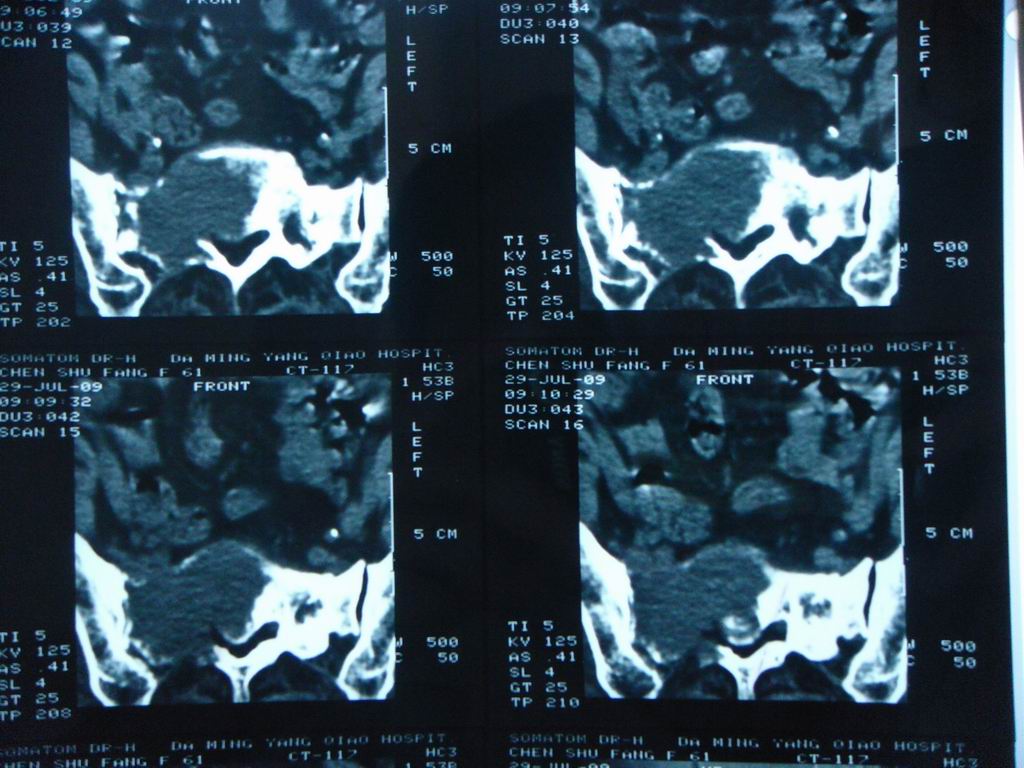

标题: CT21430:女性65岁 乳腺癌术后3年 [打印本页]

标题: CT21430:女性65岁 乳腺癌术后3年

结合病史,考虑骶骨转移瘤,但软组织肿块未突破骨壳,骨巨细胞瘤不能完全排除,骨髓瘤及脊索瘤不考虑。

结合病史,考虑骶骨转移瘤。

结合病史,考虑骶骨转移瘤。其它椎体,如腰5是否有问题呢?

个人感觉骨巨细胞瘤可能性大些。